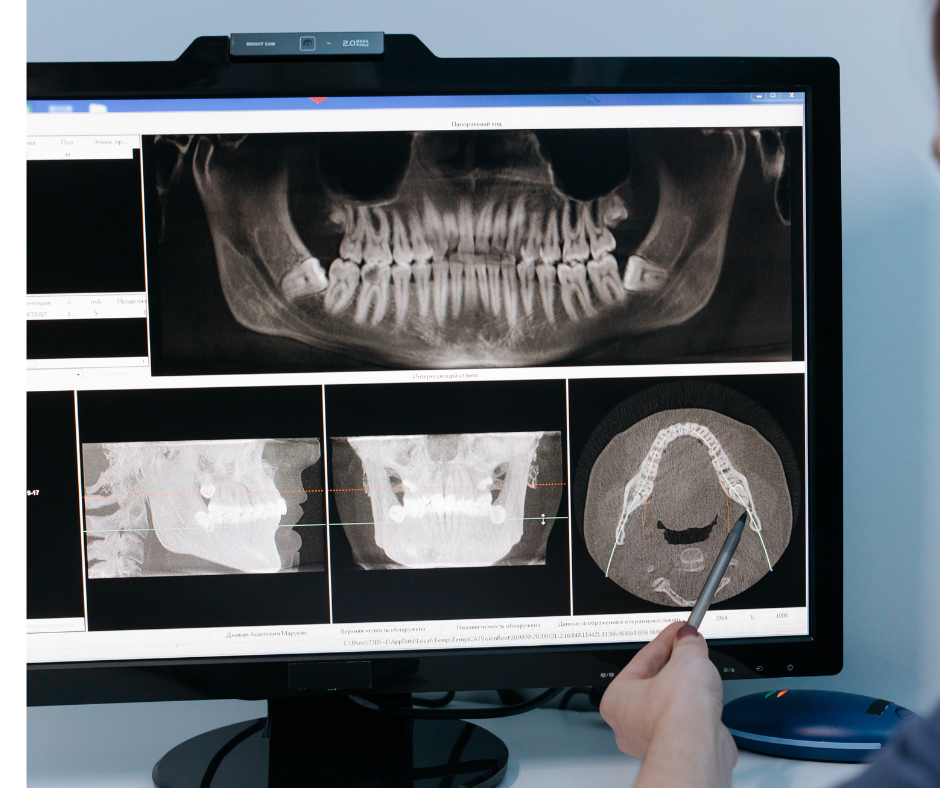

Como é feito o diagnóstico periodontal?

O diagnóstico correto envolve:

- exame clínico detalhado

- medição das bolsas gengivais

- avaliação do suporte ósseo

- exames de imagem, quando indicados

Esse processo deve ser realizado por um periodontista, profissional capacitado para diagnosticar e tratar doenças periodontais.